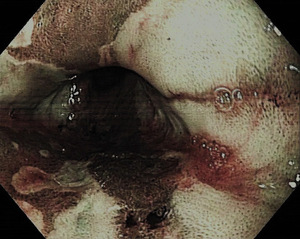

Wczesny rak przewodu pokarmowego definiowany jest jako nowotwór złośliwy pochodzenia nabłonkowego nieprzekraczający błony podśluzowej, bez cech naciekania błony mięśniowej właściwej. W przypadku wczesnego raka przełyku warunkiem rozpoznania jest wykluczenie obecności przerzutów do okolicznych węzłów chłonnych. Dokładność przedoperacyjnej oceny głębokości nacieku wczesnego raka oceniana jest na 70-95 proc. Wczesny rak może być widoczny jedynie jako zmiana zabarwienia błony śluzowej – częściej w postaci zaczerwienienia lub rzadziej – zblednięcia powierzchni. Szczególnie dotyczy to niewielkich zmian, trudnych do wykrycia w rutynowym badaniu (ryc.1). W przypadku znalezienia podejrzanej zmiany wskazane jest stosowanie barwień (płynem Lugola do nabłonka płaskiego lub indygokarminem albo błękitem metylenowym do nabłonka gruczołowego). Nowoczesne endoskopy wyposażone są w systemy powiększenia obrazu oraz systemy barwień elektronicznych oparte na oglądaniu zmian po podświetleniu ich wąską wiązką światła – (narrow band imaging NBI)(ryc. 2, 3).[2] Daje to możliwość dobrego uwidocznienia struktury powierzchni zmiany, jej granic oraz oceny rysunku naczyniowego, a co za tym idzie – wyboru optymalnego miejsca do pobrania wycinków. Tak precyzyjna ocena endoskopowa pozwala z ogromną dozą prawdopodobieństwa postawić jednoznaczne rozpoznanie, dlatego zwana jest też biopsją optyczną.[3] Tak więc decydujące znaczenie ma obraz endoskopowy: wielkość i kształt zmiany, jej typ makroskopowy określany wg klasyfikacji japońskich (ryc. 4).[4]